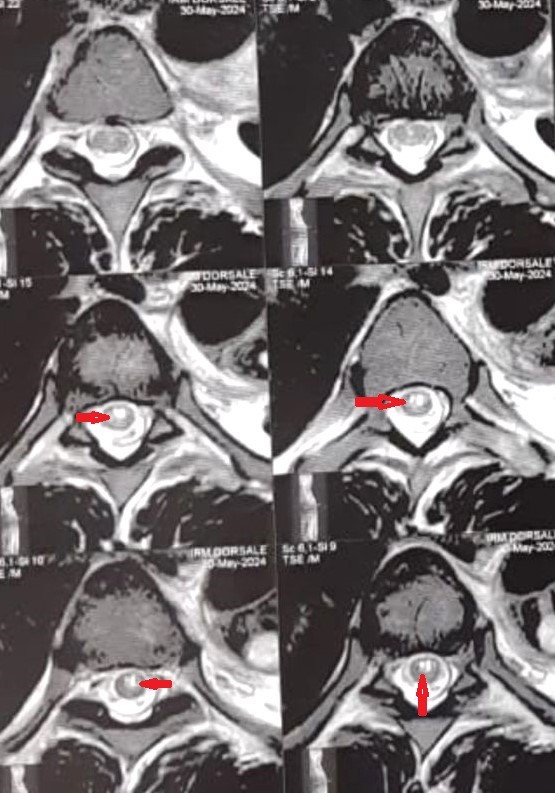

Figure 2: IRM Dorsale Coupes en séquence T2 montrant un hyper signal focal au niveau de la moelle épinière traduisant l’ischémie médullaire.